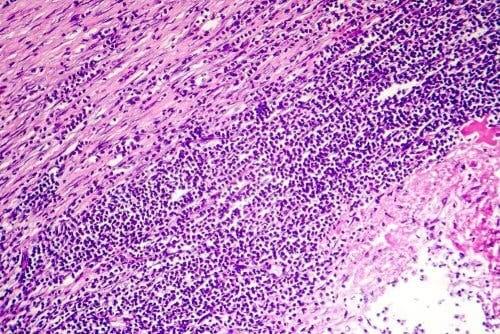

Pericarditis verwijst naar een ontsteking van het hartzakje, een zakvormig membraan dat het hart omringt. Dit membraan heeft twee lagen en daartussen zit een kleine hoeveelheid vloeistof. Dit is een glijmiddel om de twee lagen heen en weer te laten glijden.

Bij ongeveer 80% van de gevallen is het onmogelijk om de oorzaak van pericarditis vast te stellen. Het komt echter vaak voor dat de oorzaak van de pericarditis het gevolg is van een infectie.

Het is in dat geval zeer waarschijnlijk een virale infectie. Er is een kleinere kans dat het een bacteriële infectie is, en slechts zeer zelden is het het gevolg van een schimmelinfectie.